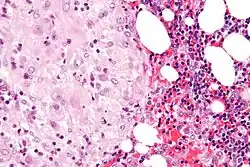

The decidua has a histologically-distinct appearance, displaying large polygonal decidual cells in the stroma. These are enlarged endometrial stromal cells, which resemble epithelium (and are referred to as "epithelioid").

Its leukocyte population is distinct, with the presence of large endometrial granular leukocytes being predominant, while polynuclear leukocytes and B cells are scant.

The large granular lymphocytes (CD56 bright) are called uterine natural killer cells| (uNK cells).

-

Acute choriodeciduitis, with neutrophils seen in the chorion and decidua.